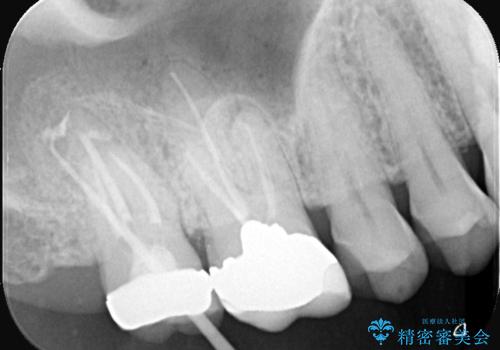

根尖性歯周炎|歯根嚢胞|インプラント治療

- 治療計画

- 右上7番に瘻孔を認め、根管治療を実施しましたが、瘻孔が再発し治癒が得られなかったため、抜歯のうえインプラントによる補綴治療を行いました。

抜歯と歯根嚢胞の除去を行った後、インプラントで治療しました。治療後は「自分の歯のように咬める」と大変ご満足いただけました。